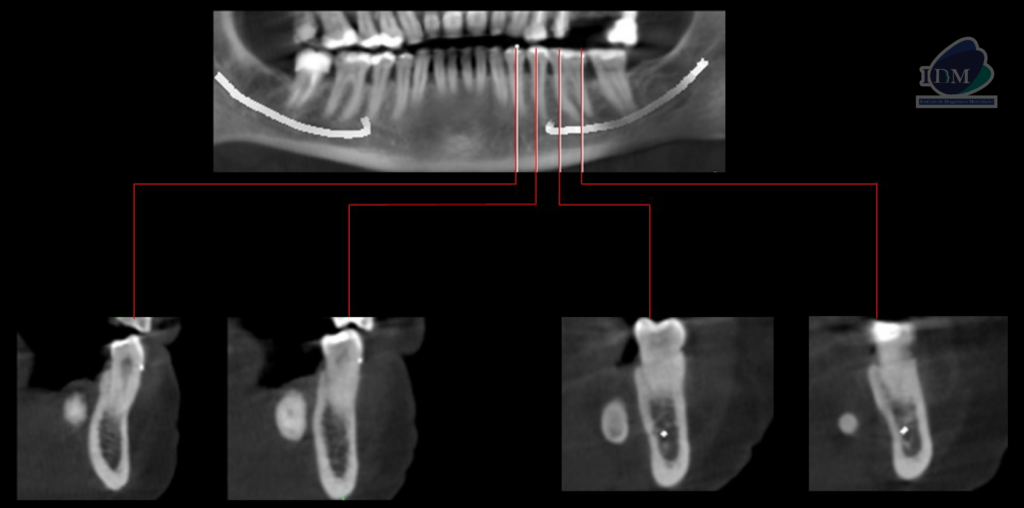

A la evaluación de la tomografía computarizada cone beam en cortes axiales, coronales y transaxiales se observa una imagen hiperdensa con una pequeña área hipodensa central que se localiza por lingual de aproximadamente 20 mm, a nivel del tercio apical de la pieza 33 hasta la raíz distal de la pieza 36. En la reconstrucción en 3D se puede observar de manera más didáctica la relación con las estructuras adyacentes y la forma que presenta, signos imagenológicos compatible con sialolito submandibular.

RECONSTRUCCIÓN 3D